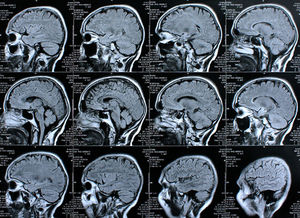

Gehirn-Screen: Rolle von Östrogen genau untersucht.